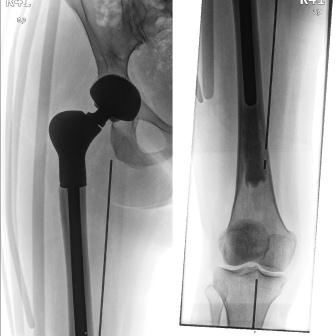

Daraufhin wurde die Patientin der Osteosarkomstudie gemeldet. Nach interdisziplinärer Diskussion im Tumorboard wurde ein primäres operatives Vorgehen mit adjuvanter Chemotherapie festgelegt. Am 24.04.2012 erfolgten intraoperativ zunächst eine Darstellung der Kapsel und eine Punktion des rechten Hüftgelenkes. Ein hämorrhagischer Erguss und somit Tumoreinbruch ins Gelenk konnte ausgeschlossen werden. Daraufhin wurde das proximale Femur bis zur geplanten Osteotomie knapp unterhalb des Trochanter minor aus den Weichteilen ausgelöst. Die Kapsel wurde vollständig am Resektat belassen, bis über den Limbus acetabuli hinaus auf das Becken und dort abgesetzt. Nach Femurosteotomie und Entfernung des Resektates erfolgte eine intensive Spülung. Anschließend wurde die Pfanne in Standardtechnik ausgefräst. Es gelang, einen 54mm-Kapuzinersockel zu implantieren, der eine anatomiegerechte Position des Drehzentrums und gleichzeitig die Verwendung eines wesentlich stabileren, weniger luxationsgefährdeten 36mm-Gelenkes gestattet. Das proximale Femur wurde anschließend mit dem MML-System versorgt, welches mit einem Trevira-Anbindungsschlauch umhüllt wurde. Es folgten die sorgfältige Rekonstruktion der verbliebenen Weichteile (M. Iliopsoas, Mm. glutaei und Tractus iliotibialis) sowie der Wundverschluss durch Subkutan- und resorbierbare Intrakutannaht. Die Patientin wurde prophylaktisch mit einer Antiluxationsorthese versorgt. Histologisch wurden die Diagnose Osteosarkom und die angestrebte R0-Resektion bestätigt. Mobilisation und Wundheilung verliefen unkompliziert. Die adjuvante Chemotherapie schloss sich an. Beim ersten Re-Staging 6 Monate postoperativ gab es keine Hinweise auf ein lokales Rezidiv oder auf Metastasen. Die Patientin ist mit UA-Stützen mobil. Bisher gab es keine Luxations- oder Subluxationsereignisse. Die aktuellen Röntgenaufnahmen zeigten einen korrekten lockerungsfreien Sitz der Implantate (Abb. 2).